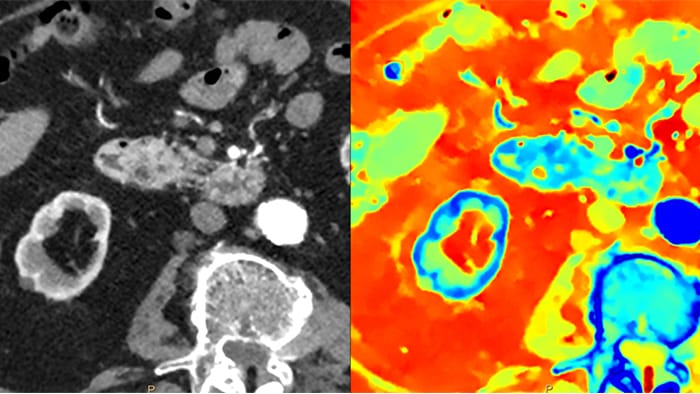

A differenza delle immagini TC tradizionali, le immagini della TC basata su detettore spettrale catturano le informazioni spettrali per il 100% del tempo, senza pianificazione o configurazione speciali. Ciò significa che è possibile analizzare in retrospettiva i dati spettrali di qualsiasi immagine, utilizzando diversi strumenti di visualizzazione spettrale. È possibile, ad esempio, regolare il livello monoenergetico oppure ottenere la mappa Zeffective.

Il detettore spettrale assorbe e differenzia simultaneamente l'energia alta e bassa da un singolo fascio di raggi X polienergetici. I risultati spettrali vengono acquisiti all'interno di una singola scansione senza la necessità di ricorrere a modalità speciali.

La TC basata su detettore spettrale assorbe e differenzia simultaneamente, a livello del detettore, l'energia alta e bassa, in un singolo fascio di raggi X polienergetici.